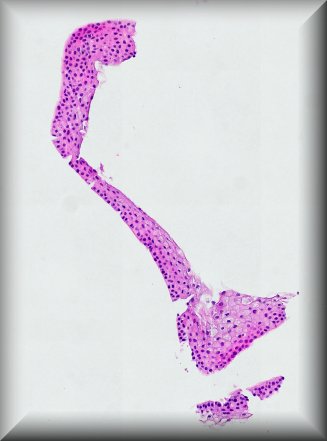

Jolique van Ipenburg (Nijmegen): 50-year-old male, retinoblastoma survivor, with conjunctival squamous lesion. Protocol |